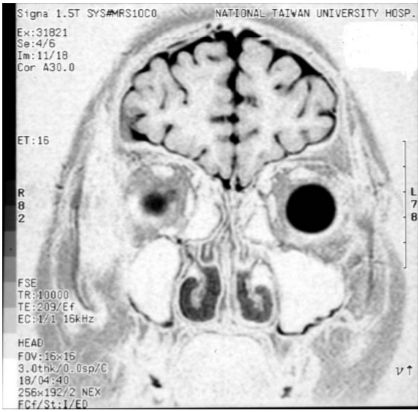

4. 23歲男性兵役體檢發現性器發育不良,MRI如圖,最可能的診斷是: (A) Pseudohermaphroditism (B) Klinefelter syndrome (C) Noonan syndrome (D) Prader-Willi syndrome (E) Kallmann syndrome